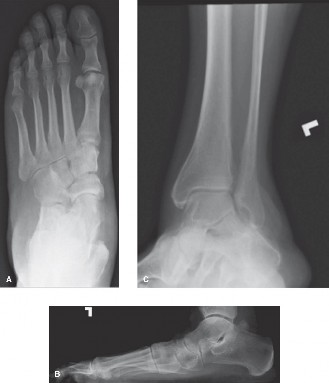

A 39-year-old female presents with increasing pain over the lateral aspect of her foot. She complains of diff…